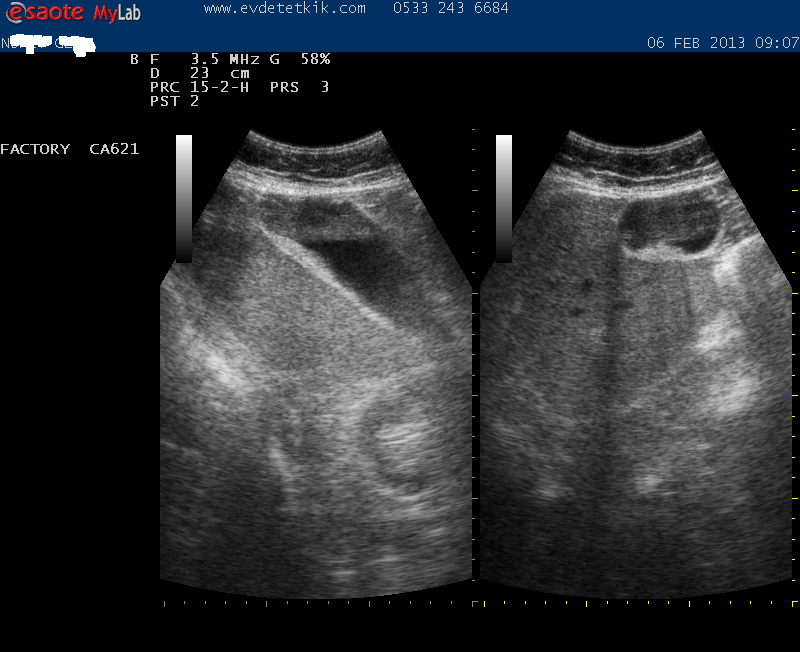

Hizmetimizden görüntüler